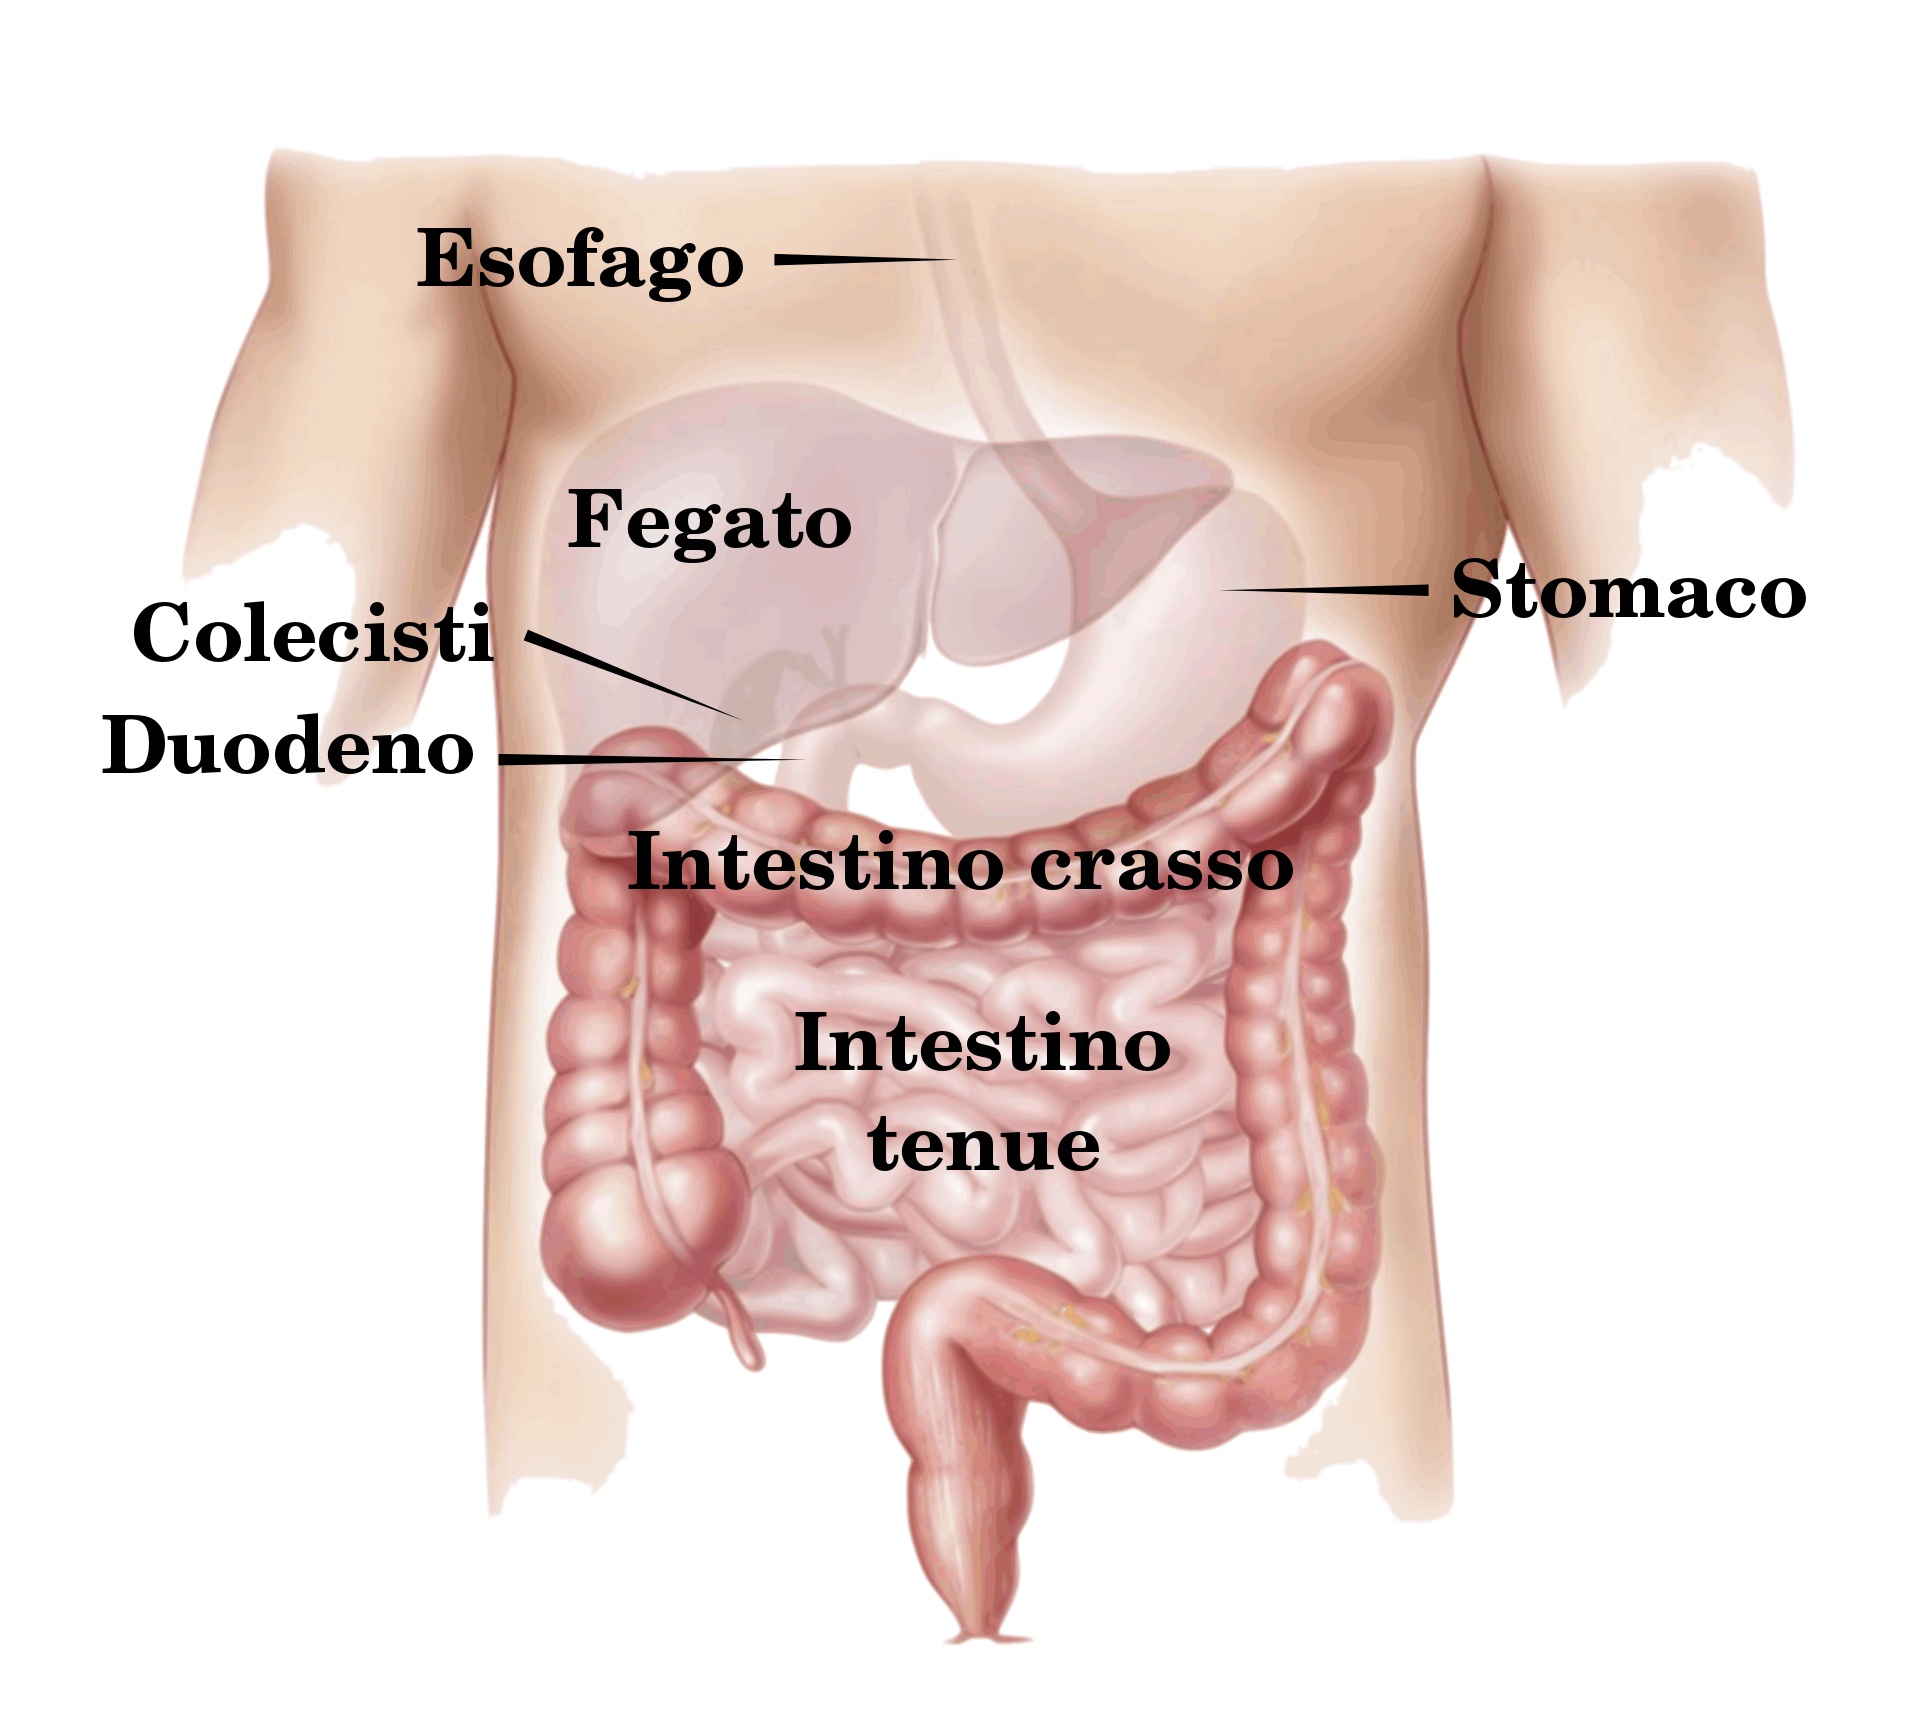

La poltiglia che abbiamo ottenuto in bocca masticando del cibo passa attraverso l’esofago e raggiunge lo stomaco, dove incontra i succhi gastrici che disgregano il nostro pasto in sostanze più semplici, per essere digerite nel passaggio successivo nell’intestino tenue. Qui viene estratta la maggior parte dei nutrienti e ciò che rimane raggiunge l’intestino crasso, che è formato dalla sua porzione iniziale (il “cieco”), dal colon e infine dal retto. Il crasso si occupa di estrarre ancora qualche nutriente da ciò che rimane e soprattutto la maggior quantità possibile di acqua. È un lavoro duro e un po’ pericoloso che avviene tra batteri e sostanze di scarto, ma qualcuno dovrà pur farlo.

(Wikimedia)